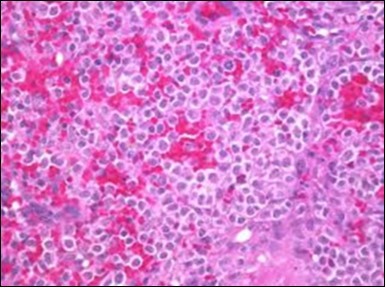

The leukaemia cells may enunciate a characteristic immune phenotype, crucial for a confirmatory diagnosis. The peripheral blood mononuclear B cell population may display a kappa or lambda light chain restriction. The phenotype of classic hairy cell leukaemia may be delineated by concurrent, immune reactive CD19+ CD20+,CD 11c+, CD25+, CD103+ and CD123+. An intensely immune reactive CD200+ and a non reactive CD27- antigen may be present2, 4. Evaluation of a trephine bone marrow biopsy and bone marrow aspirate may define the degree of tumour infiltration. A dry tap on account of prominent bone marrow fibrosis may be elucidated at preliminary diagnosis. A decline in the normal haematopoiesis may account for a hypo-cellular marrow in 10% instances. Gradation of cellular infiltrating of the leukaemia within the bone marrow may be appropriately investigated with immune –histochemical stains2, 4. Immune staining for CD20+, annexin 1 and VE1 (a BRAF V600E stain] may validate the diagnosis and precisely analyse the extent of malignant bone marrow infiltration[8]. Determination of BRAF V600E mutation may be critical in therapeutically non responsive individuals with applicable standard therapy or in instances of multitudinous reoccurrences[9]. Deploying inhibitors of BRAF V600E gene may be efficacious in patients impervious to approved therapy. The mutation necessitates a comprehensive scrutiny of the implicated individuals with a sensitive molecular assay which may discern up to < 10% of the hairy leukaemia cells appearing in the peripheral blood smears or bone marrow aspirates diluted with peripheral blood or aspirates elucidating a dry tap[2,4]. Allele specific polymerase chain reaction (PCR) or a next generation sequencing may be optimally employed to circumvent false negative outcomes. If the leukaemia cells are sparse or if particularly sensitive & efficacious molecular techniques are not accessible, the application of appropriate immune histochemical stains to the bone marrow biopsy such as a BRAF V600E mutation stain (VE1) may detect the hairy cells and conclusively diagnose the condition[2,4,10]. Figure 1, Figure 2, Figure 3, Figure 4, Figure 5, Figure 6, Figure 7, Figure 8, Figure 9, Figure 10, Figure 11, Figure 12, Figure 13, Figure 14.

Figure 1.HCL: hairy cells infiltrating designated spaces(17).

Figure 2.HCL: hairy cells with projecting cytoplasm abutting bony trabaculae(18).

Figure 3.HCL: hairy cells dispersed within the native architecture(19).

Figure 4.HCL: hairy cells with widely spaced nuclei(20).

Figure 5.HCL: hairy cells with infiltration in the spleen(21).

Figure 6.HCL: disseminated hairy cells with a clear cytoplasm(22).

Figure 7.HCL: blebs on the cellular surface with fine nuclear chromatin(23).

Figure 8.HCL: widely disseminated hairy cells within the bone marrow trabaculae(24).

Figure 9.HCL: hairy cells within a bone marrow trephine biopsy(25).

Figure 10.HCL: inconspicuous nucleoli, open-ended chromatic and surface protrusions(26).

Figure 11.HCL Oral mucosa with soft tissue infiltration of hairy cells(27).

Figure 12.HCL: hairy cells with broad and fine projections of the cytoplasm(28).

Figure 13.HCL: hairy cells immune reactive for CD 11c(24).

Figure 14.HCL: hairy cells with demonstrable tartrate resistant acidic phosphatise( TRAP) stain(29).